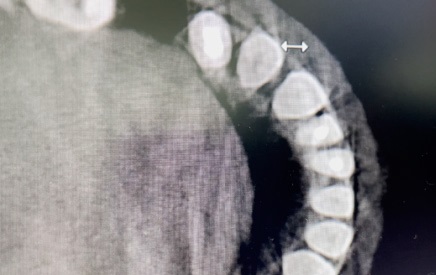

Diagnostyka przy użyciu tomografii komputerowej, leczenie w powiększeniu przy zastosowaniu mikroskopu zabiegowego, wsparcie laserowe poprzez fotobiomodulację celem zmniejszenia dolegliwości bólowych i przyspieszenia gojenia – to jedno z wielu udoskonaleń technologicznych, jakie w znaczący sposób przyczyniają się do sukcesu terapeutycznego. Prezentowany w artykule opis przypadku dotyczy 37-letniej pacjentki, która zgłosiła się z bólem w obrębie zębów 32 i 31. Tomografia komputerowa z wiązką stożkową (CBCT) ujawniła rozległe zmiany zapalne w tkankach okołowierzchołkowych z utratą blaszki przedsionkowej kości żuchwy przy zębach 32 i 31. Po szczegółowej diagnostyce podjęto decyzję o przeprowadzeniu leczenia endodontycznego podczas jednej wizyty. Zastosowano opracowanie chemo-mechaniczne kanałów przy użyciu narzędzi maszynowych Reciproc oraz obfitą irygację z użyciem 5,25% NaOCl, 40% kwasu cytrynowego, 0,9% NaCl. Obturację kanałów wykonano za pomocą kondensacji pionowej gutaperki na ciepło z użyciem uszczelniacza AH Plus. Celem polepszenia samopoczucia pacjentki i rokowań pozabiegowych przeprowadzono fotobiomodulację laserową, wykorzystując laser SMARTMPRO. Po 8 miesiącach kontrolne CBCT wykazało niemal całkowite wygojenie się zmian.

Cone Beam Computed Tomography diagnostics, magnification treatment using a surgical microscope, laser support through photobiomodulation to reduce pain and accelerate healing – these are just one of many technological improvements that significantly contribute to therapeutic success. The case report concerns a 37-year-old female patient who presented with pain in the area of teeth 32 and 31. The CBCT showed extensive periapical changes with loss of the vestibular bone of the mandibula at the abovementioned teeth. After detailed diagnostics, it was decided to carry out endodontic treatment during one visit. The chemo-mechanical treatment of the canals was applied using Reciproc machine tools and abundant irrigation with the use of 5.25% NaOCl, 40% citric acid and 0.9% NaCl. The obstruction of the canals was done by warm vertical condensation of gutta-percha and by using AH Plus sealant. In order to improve the patient’s well-being and postoperative prognosis, laser photobiomodulation was performed using the SMARTMPRO laser. After 8 months, the control CBCT showed almost complete healing of the lesions.